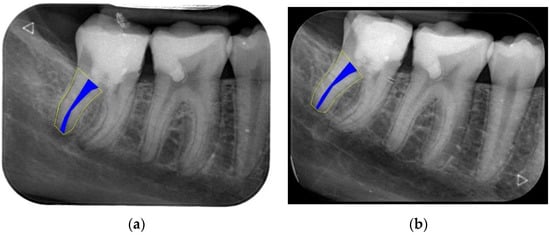

We clinically assessed the outcomes in the absence of any signs and symptoms and a negative cold-sensitivity test. Periapical healing, root elongation, RRA, and apical closure were assessed radiographically (Figure 1a,b). For this, we re-sized the immediate postoperative and follow-up periapical radiographs to match the size and pixels. We used the Freeware Image J software (version 1.47; National Institutes of Health, Bethesda, Rockville, MD, USA) together with the TurboReg plugin tool (Philippe Thevenaz, Biomedical Imaging Group, Swiss Federal Institute of Technology Lausanne, Lausanne, Switzerland) Rasband 1997–2018 [28] as described by Kahler et al. [29]. In brief, for radiographs obtained using different imaging systems, we used the ‘Images to Stack’ and ‘Stack to Images’ functions to equalise the number of pixels in the radiograph. Subsequently, the radiographs of each case were aligned and normalised using the TurboReg plugin tool. This tool enabled the measurement of curved roots (Figure 2a,b). Two evaluators (RY and AYK) conducted the calibration sessions using instructional videos. All cases were separately reviewed by two calibrated examiners. They discussed the case upon obtaining dissimilar results until it was resolved. The above-mentioned changes in root dimension were calculated as a percentage (Figure 3a,b). Hence, we evaluated the effect of the treatment based on the relative increase in RRA and root length.

Figure 2.

The measurement of RRA in a posterior root (a) at the end of REP, (b) at the 18-month follow-up. Complete healing and apical closure are observed.